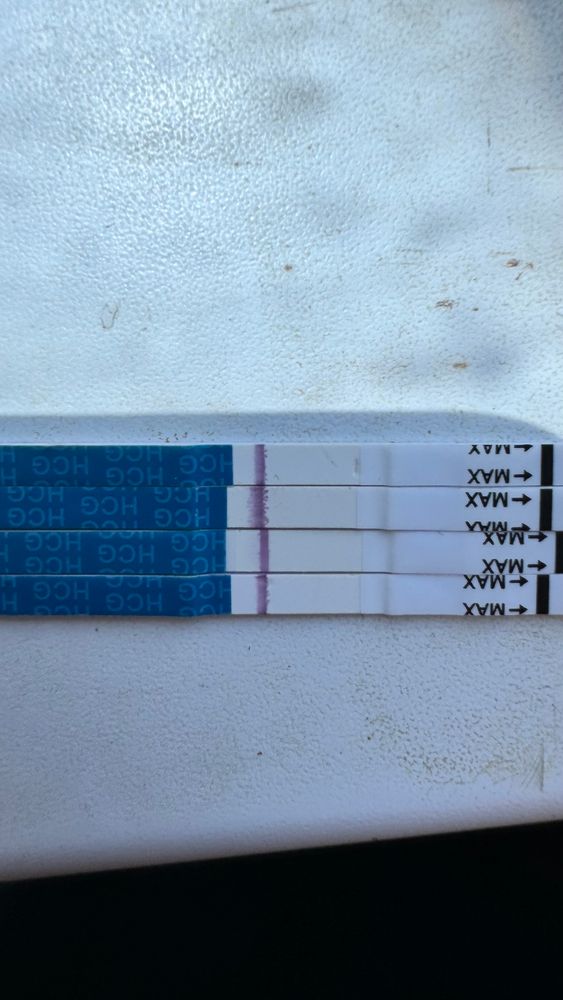

Девочки делала тесты начиная с 8 пдо , не знаю зачем 😂тапки не кидать ) последний тест 11пдо , я вижу тень , все тесты с одной пачки мама чек. Что думаете ?

Девочки делала тесты начиная с 8 пдо , не знаю зачем 😂тапки не кидать ) последний тест 11пдо , я вижу тень , все тесты с одной пачки мама чек. Что думаете ?

Тут явно место под полоску на всех. Для 10-11 ну это совсем слабо. Вечером повторите. Мои всегда вечером ярче. Мало ли, может и у вас так